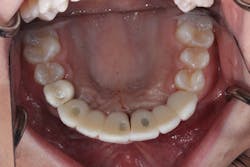

The patient was allowed to heal for three months before returning to uncover the implants. Full thickness flap incisions and retraction of Nos. 5–11 noted bone growth over the implants. We placed polyetheretherketone (PEEK) abutments over the implants to fabricate a fixed screw-retained provisional chairside (figure 9). We grafted once again with PRF, mineralized freeze-dried bone allograft, and fusion bone binder to thicken the area. One horizontal suture was placed from Nos. 7–10. One vertical mattress suture was placed around the No. 5 implant to obtain secondary healing, tucking the PRF membranes over the bone graft on the buccal and lingual tissue and keeping them exposed on the occlusal surface where the temps were screwed in (figure 10) . We allowed this to heal for two months before bringing the patient back to start the restorative phase of treatment (figure 11). During this time, the tissue was able to thicken with the added PRF and additional bone graft added around the implants.

Figure 11: Healed for two months and ready for final impressions